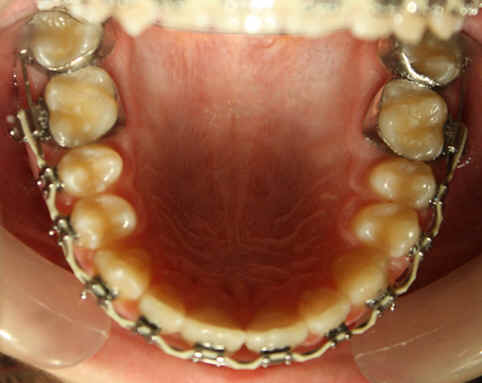

2009/10/31 U .016x.022, L to be .016 Niti

2009/12/19 U .016x.022, L .016 x .022 Niti